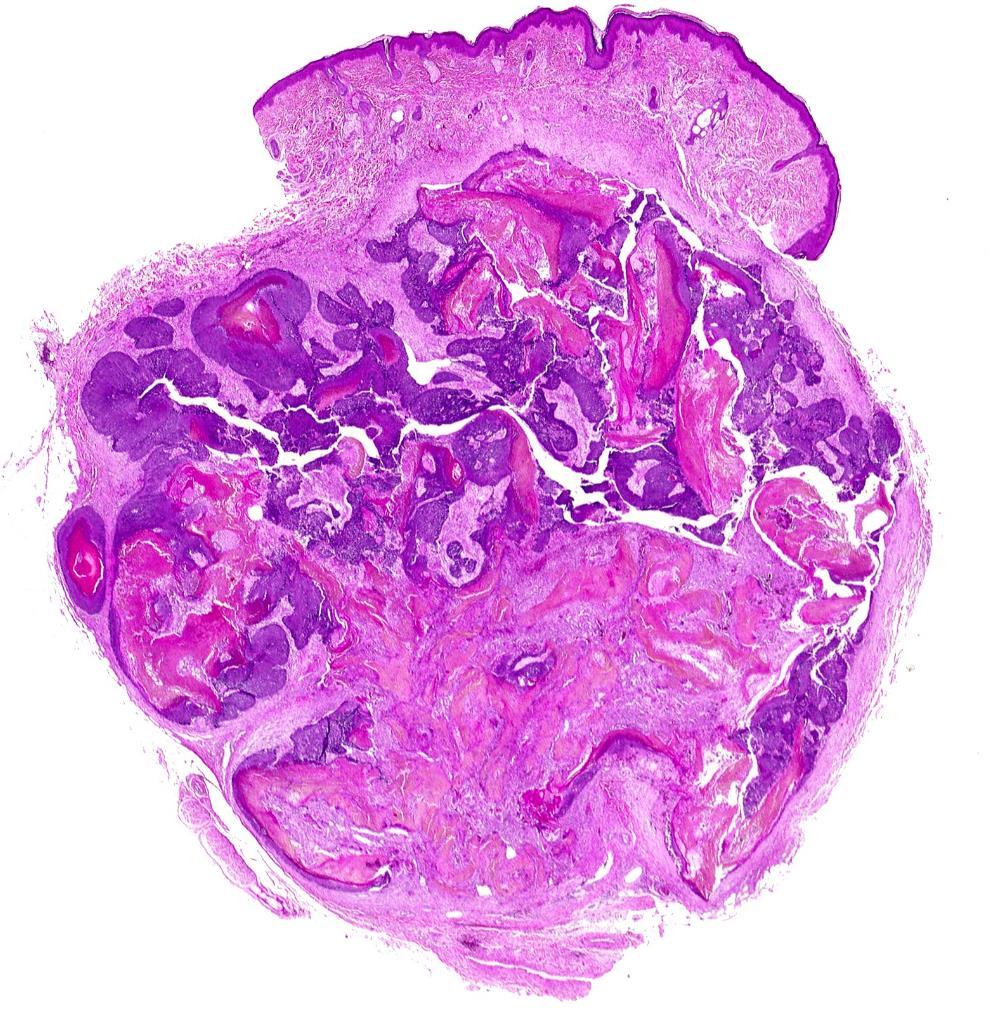

• Spiradenoma

• Multinodular benign eccrine gland derived

• Face/upper trunk

• Admixed basaloid and clear cells

• Brooke-Spiegler syndrome - CYLD

• Cylindroma

• Head and neck

• Well defined nests of basaloid cells in a jigsaw pattern with eosinophilic PAS positive basement membrane-type material

• Brooke-Spiegler syndromeCYLD